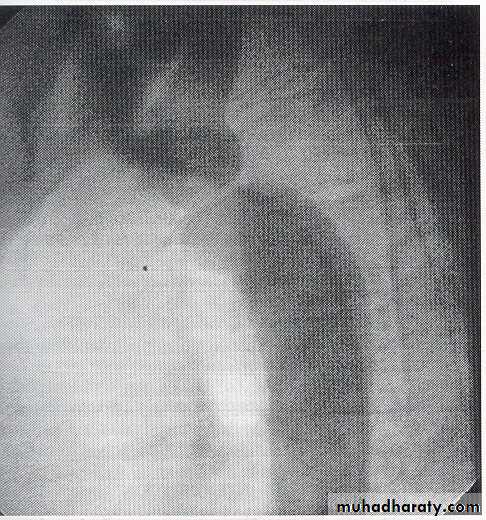

Chest X-ray in early childhood is often normal but later may show changes in the contour of the aorta (indentation of the descending aorta, ‘3 sign’) and notching of the under-surfaces of the ribs from collaterals.

"pre-stenotic and post-stenotic dilatation to form “3” shape"

chest X-ray shows an abnormally small pulmonary artery and a ‘boot-shaped’ heart.